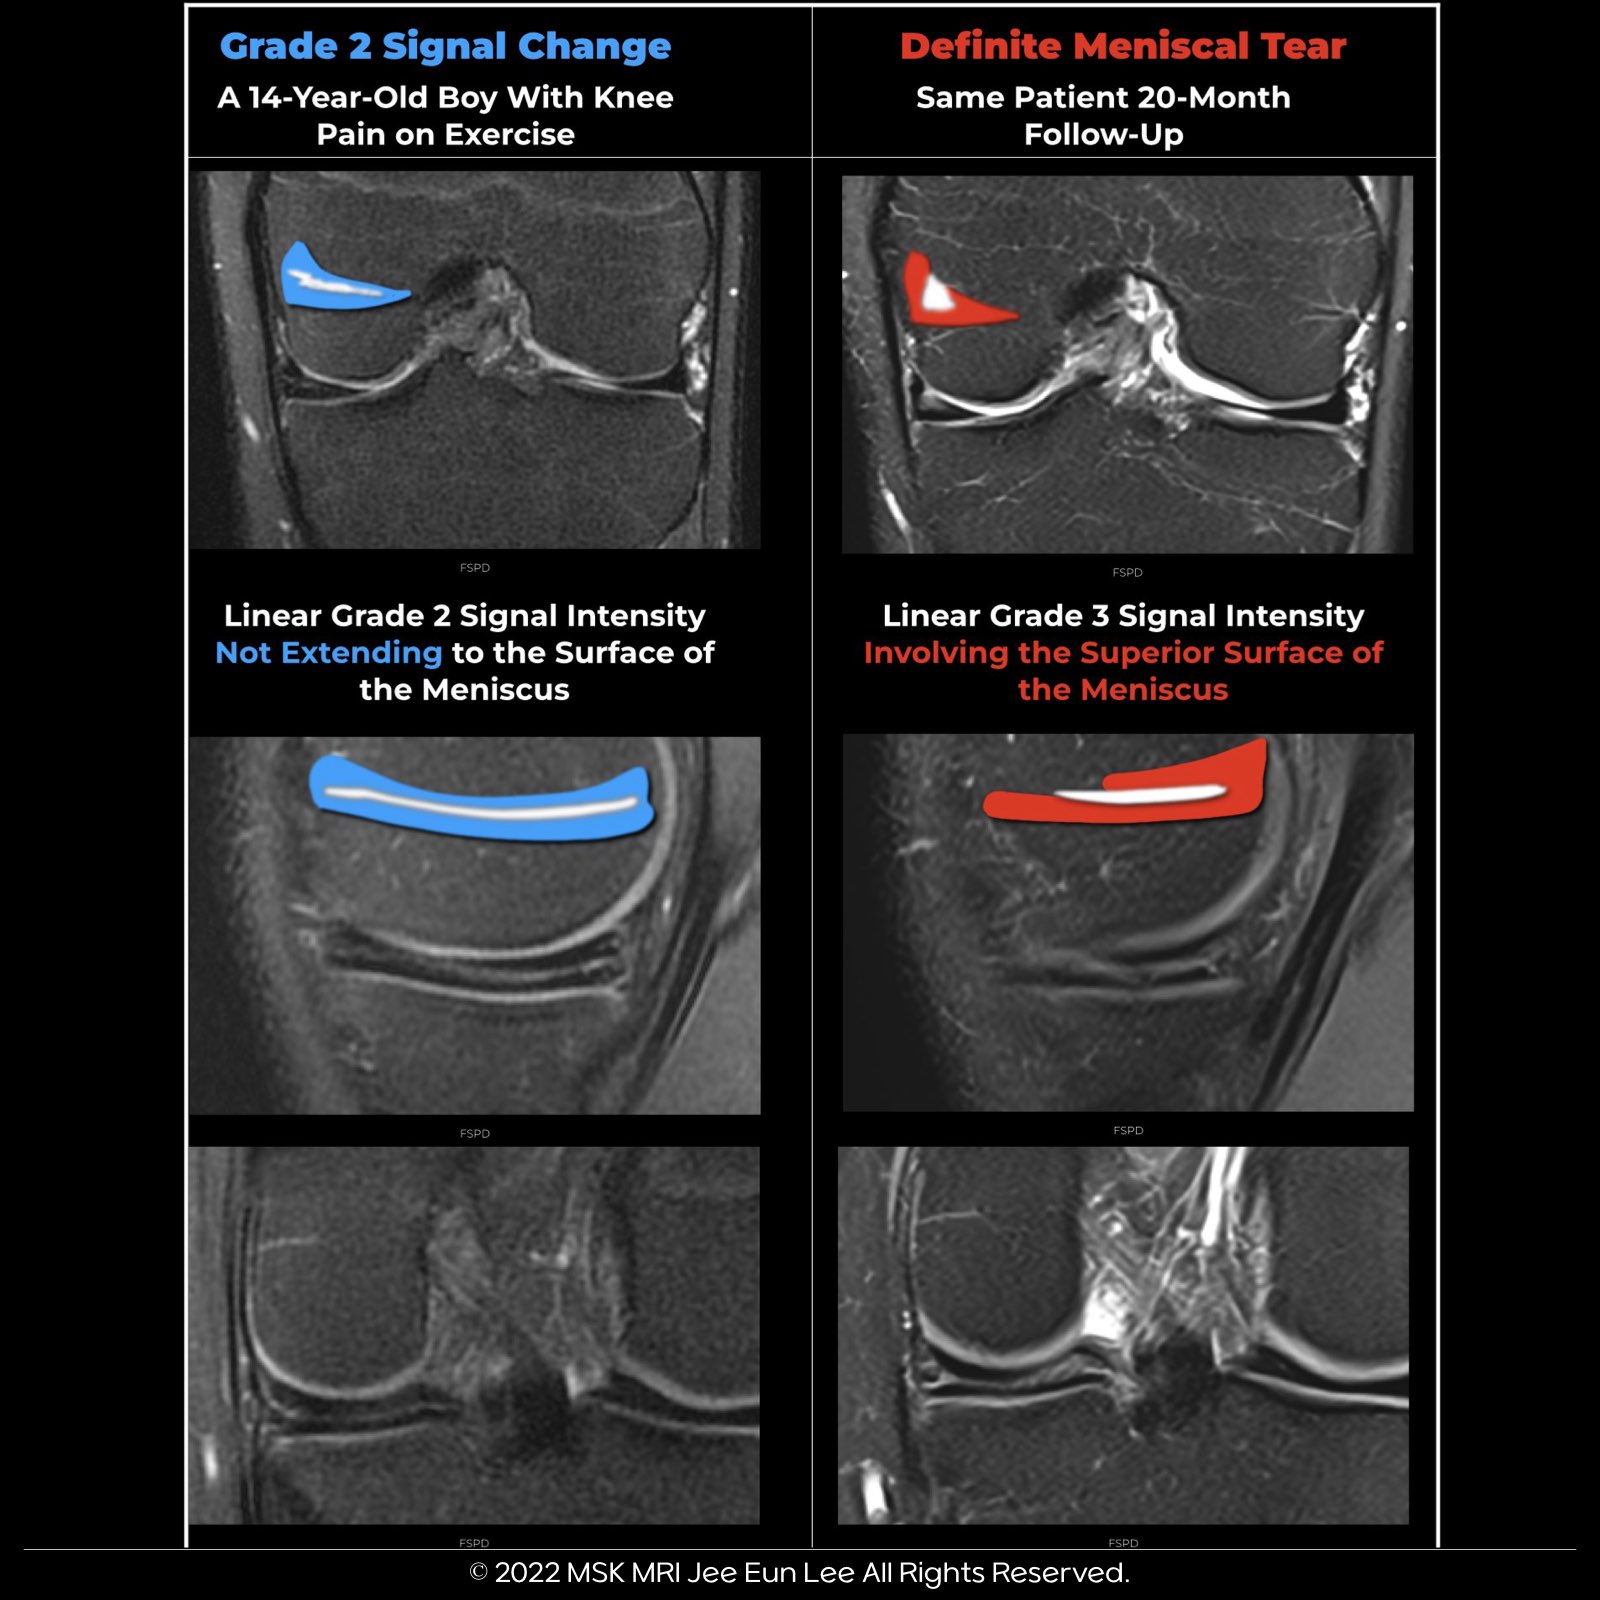

- Horizontal, linear intrasubstance signal increases from the meniscus's capsular periphery without reaching an articular surface.

- Lacks a distinct cleavage plane or tear.

- Not a prognostic indicator for advancing to grade 3 signal intensity.

- Extensive triangular or wedge-shaped signals on multiple MRI images do not reach the meniscal surface.

- Low incidence (1.5%), with a 50% chance of indicating a tear.